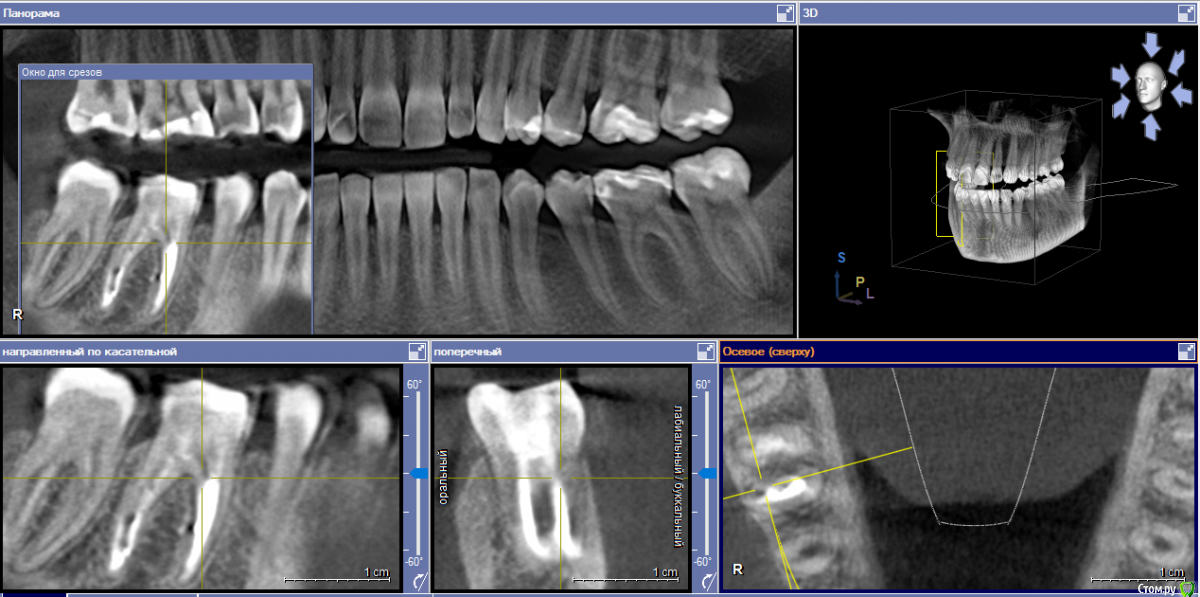

yellowborodova Опубликовано 5 января, 2020 Автор Поделиться Опубликовано 5 января, 2020 Здравствуйте... всех с праздником)) прошу прощения, что так долго... вот срезы кт и панорама. Надеюсь, заскринила то, что нужно)) буду рада, если у кого-либо будет желание и возможность прокомментировать тему. Ссылка на комментарий

yellowborodova Опубликовано 5 января, 2020 Автор Поделиться Опубликовано 5 января, 2020 Ссылка на комментарий